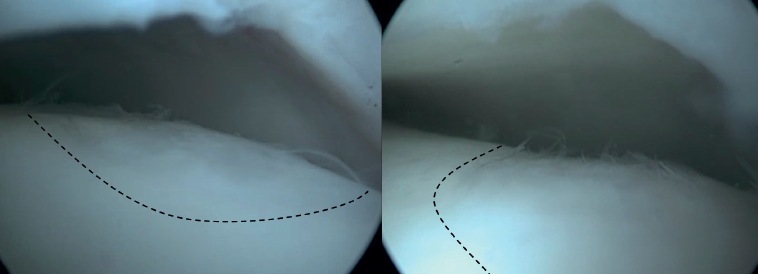

Arthroscopic Bone Marrow Stimulation (BMS) is the most frequently used treatment for primary OLT(22). BMS can be deployed for relatively smaller (<15 mm), non-cystic, non-fixable lesions(20,23). Arthroscopic BMS starts with debridement and curettage of the defective cartilage and subchondral bone(24). Subsequently, drilling or perforation of the sclerotic bone at the base of the defect is performed, often using a Kirschner wire or microfracture awl(25). The holes should be made to a depth that results in bleeding of the subchondral bone or the presence of fat droplets(23)(Figure 4). This technique disrupts the intraosseous blood vessels, leading to the subchondral bone bleeding and the formation of a fibrin clot. The release of mesenchymal blood cells promotes vascularization which induces the formation of fibrocartilage(26). When an isolated (i.e., no other damage to bone/within the joint) cartilage lesion with a macroscopically intact subchondral bone layer, is present, debridement only can be performed(27).